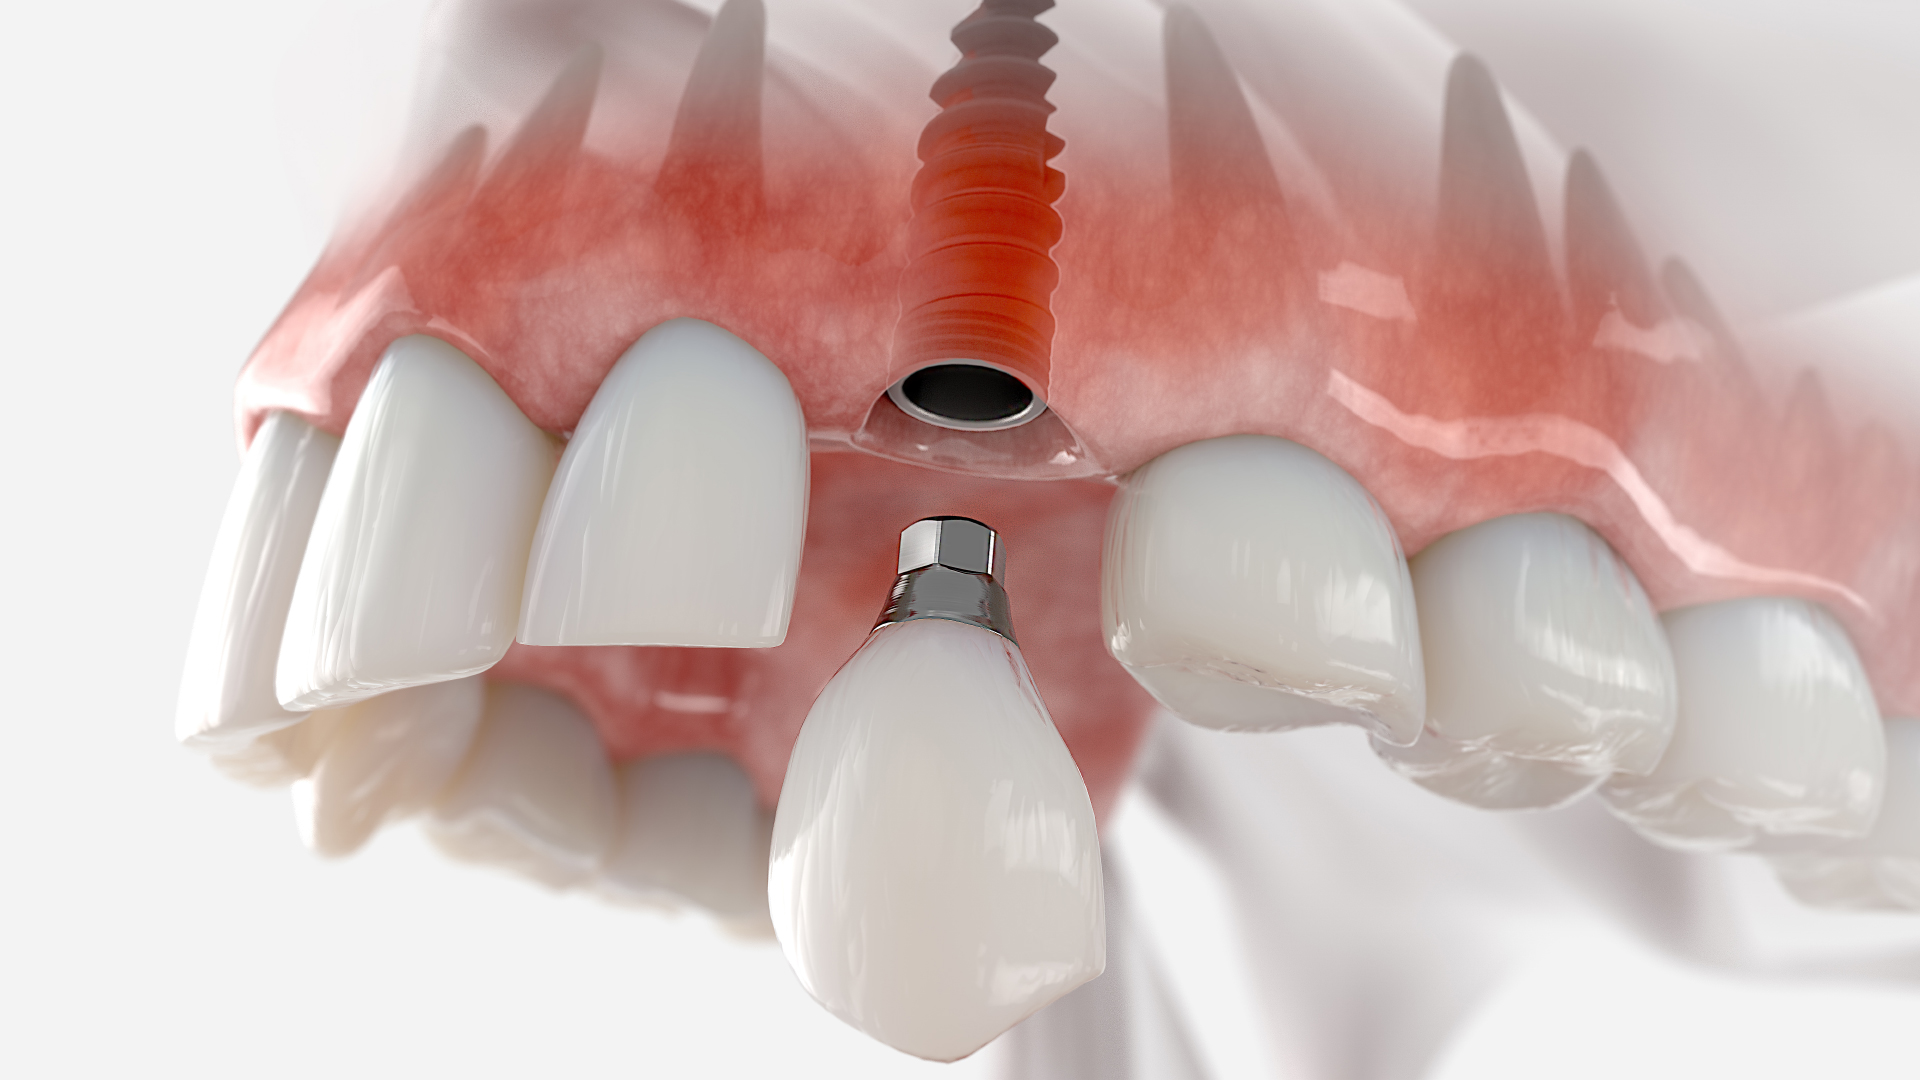

There will be a few months’ wait after implantation so there can be osseointegration, or joining of the jawbone and implant. A crown is placed to rebuild appearance and functionality after the implant is placed, so a natural-looking tooth is restored.

It’s possible to place a prosthetic tooth in an immediate loading dental implant a week after implantation, according to current method. Less time for treatment and earlier aesthetic appearance reconstruction are a couple of the benefits of this course of action. Clinical trials have demonstrated that comparable patient-reported outcomes may be obtained from both immediate and conventional loading practices.